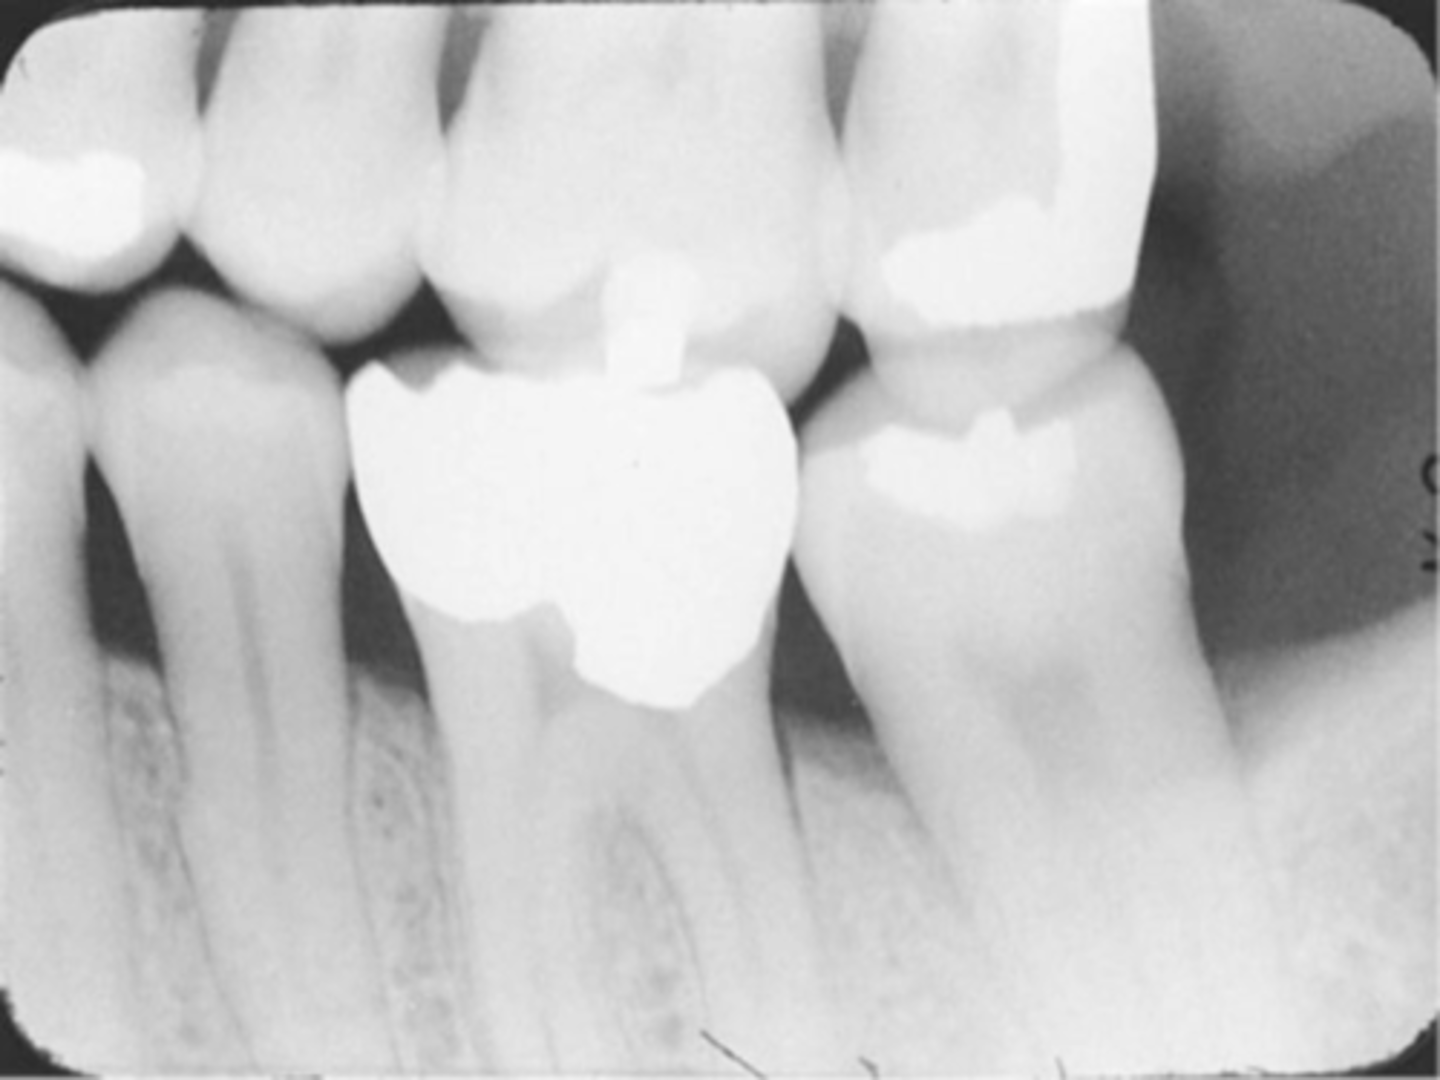

Incorrect Vertical Angulation -->Bite-Wing

-Images appears distorted

-Negative angulation was used

-To avoid always use a +10 degree vertical angulation with the bite-wing technique to compensate for the slight tilt of max teeth and slight lingual bend of the upper half of the receptor caused by the hard palate.

Film Bending

-Images appear stretched and distorted

-Film was bent excessively because of the curvature of the patient's hard palate

-Cotton rolls can be used to prevent this for the paralleling and bisecting technique or a film holding device.